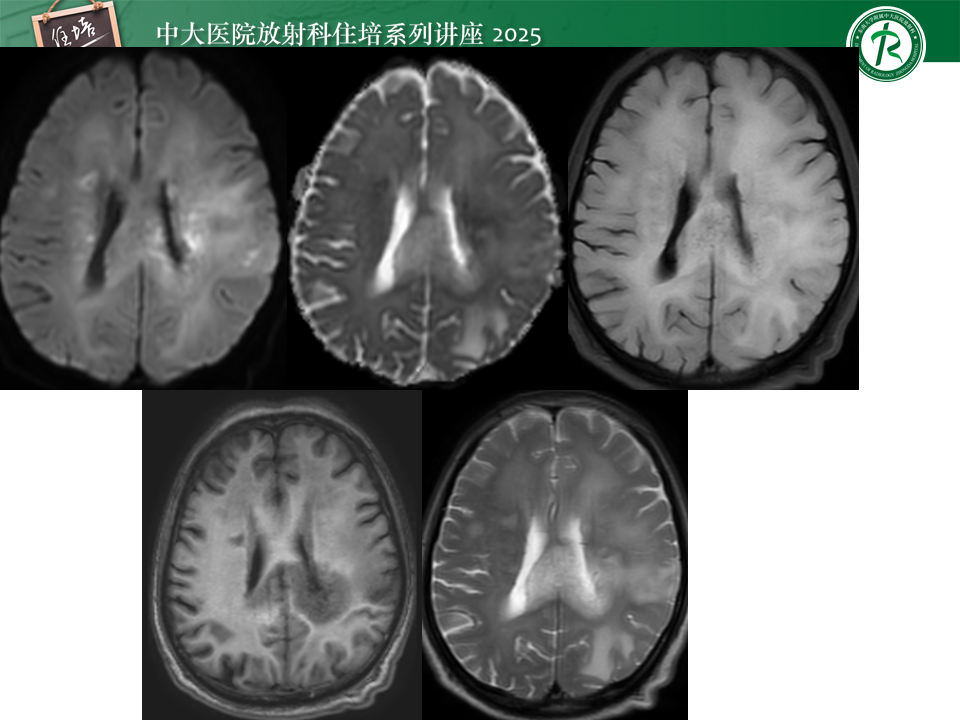

跨中线的脑内占位的影像分析思路